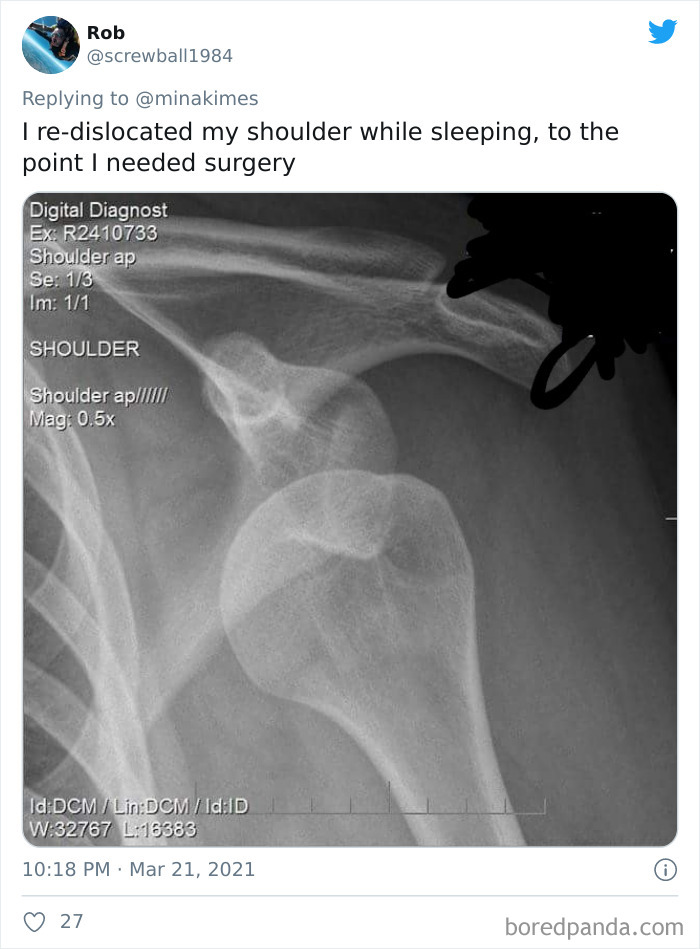

Load More Replies...Wait until you're old. You'll wake up aching somewhere even though you did nothing other than sleep. It can even last days/weeks. I threw out my shoulder...Sleeping...SMH.